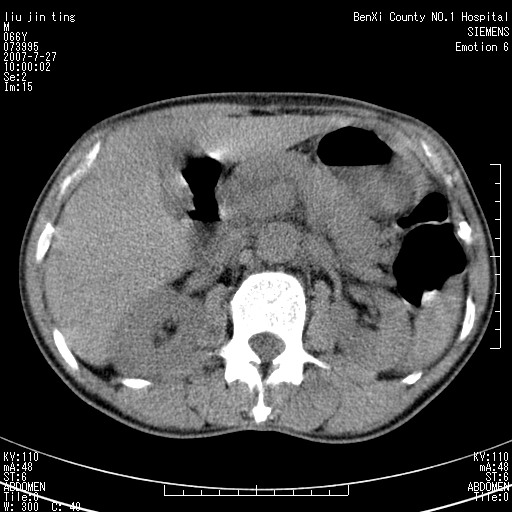

腹痛,背痛,无恶心呕吐,不黄,彩超示胰腺钩癌,ct扫描病灶平扫30-40hu,增强后动脉期40--60hu,静脉期50-68hu,真的是钩突上的么?您要试一试么?

沿着肠系膜上动脉呈匍匐性生长的软组织肿块,形态不规则,包绕肠系膜上动脉,呈明显强化,考虑来源于肠系膜的恶性肿瘤

沿着肠系膜上动脉呈匍匐性生长的软组织肿块,形态不规则,包绕肠系膜上动脉,呈轻-中度强化,考虑来源于肠系膜的恶性肿瘤。

钩突是正常的,只见腹膜后淋巴结的肿大,考虑淋巴瘤或转移可能。

支持!恶性纤维组织细胞瘤可能,与淋巴瘤及淋巴结转移鉴别(腹主动脉周围清晰,其他部位亦未见明显肿大淋巴结)。

考虑为腹膜后恶性纤维组织细胞瘤。